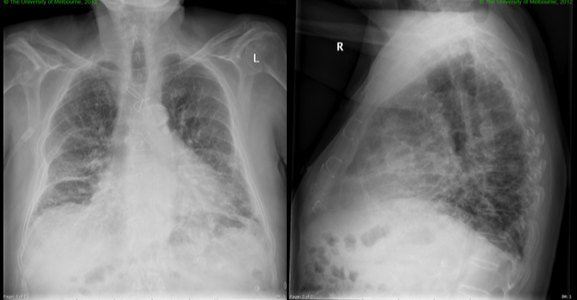

75yo male with CHF presents with dyspnoea. Crackles are heard at the lung bases on examination

Pulmonary oedema